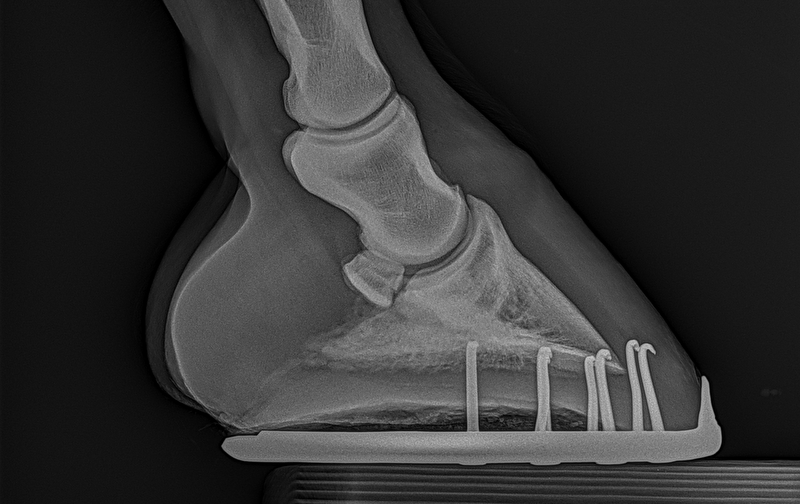

Insups schreef:Ik heb in 2022 een paard gekocht en volledig laten keuren. Die was door dierenarts 1 volledig in orde verklaard. Nu worden er nieuwe foto's gemaakt en blijkt hier toch een opmerking te zijn... Puur uit interesse ben ik benieuwd naar wat jullie zien